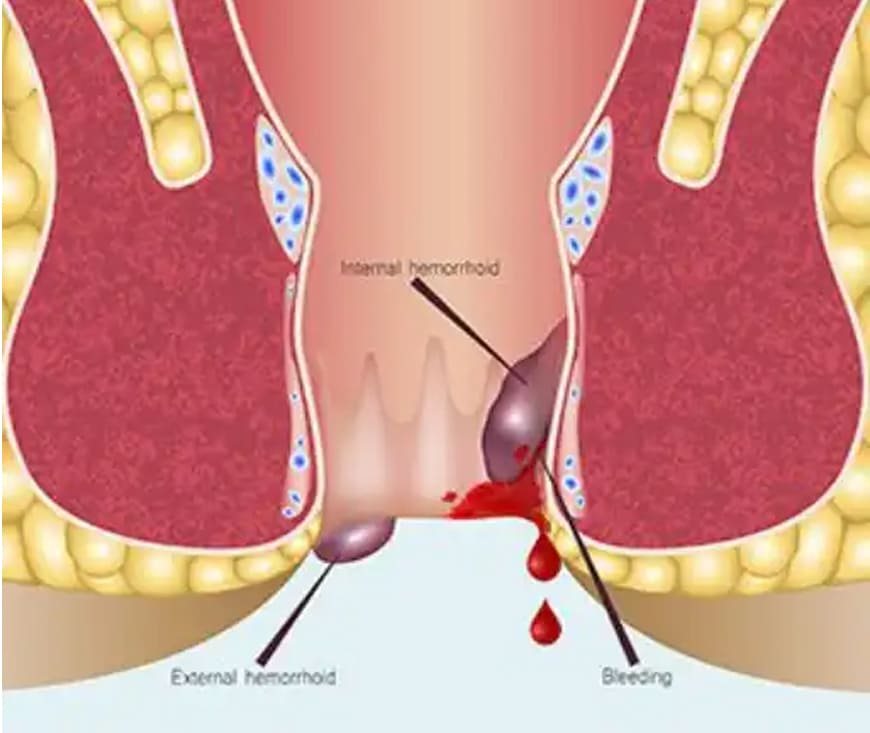

Fissures, or anal fissures, are small tears in the skin around the anus, causing pain

and discomfort. Treatment involves using stool softeners to ease bowel movements, warm

sitz baths to soothe the area, and topical creams or ointments like hydrocortisone to

reduce inflammation. In some cases, surgery may be needed for chronic fissures.

Piles, or hemorrhoids, are swollen blood vessels in the rectal area causing pain, itching, or bleeding. Treatment includes topical creams or ointments for relief, stool softeners, and warm sitz baths. For more severe cases, rubber band ligation or surgery may be necessary. A high-fiber diet and regular exercise can help prevent recurrence. Consult a healthcare provider for appropriate treatment.